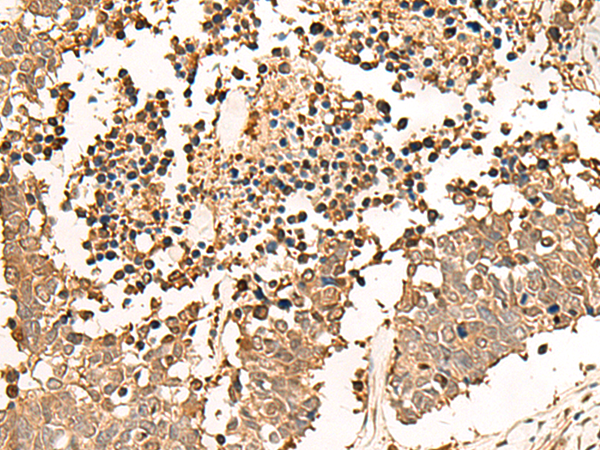

IHC positive control:

Human esophagus cancer and Human lung cancer

IHC Recommend dilution:

30-150